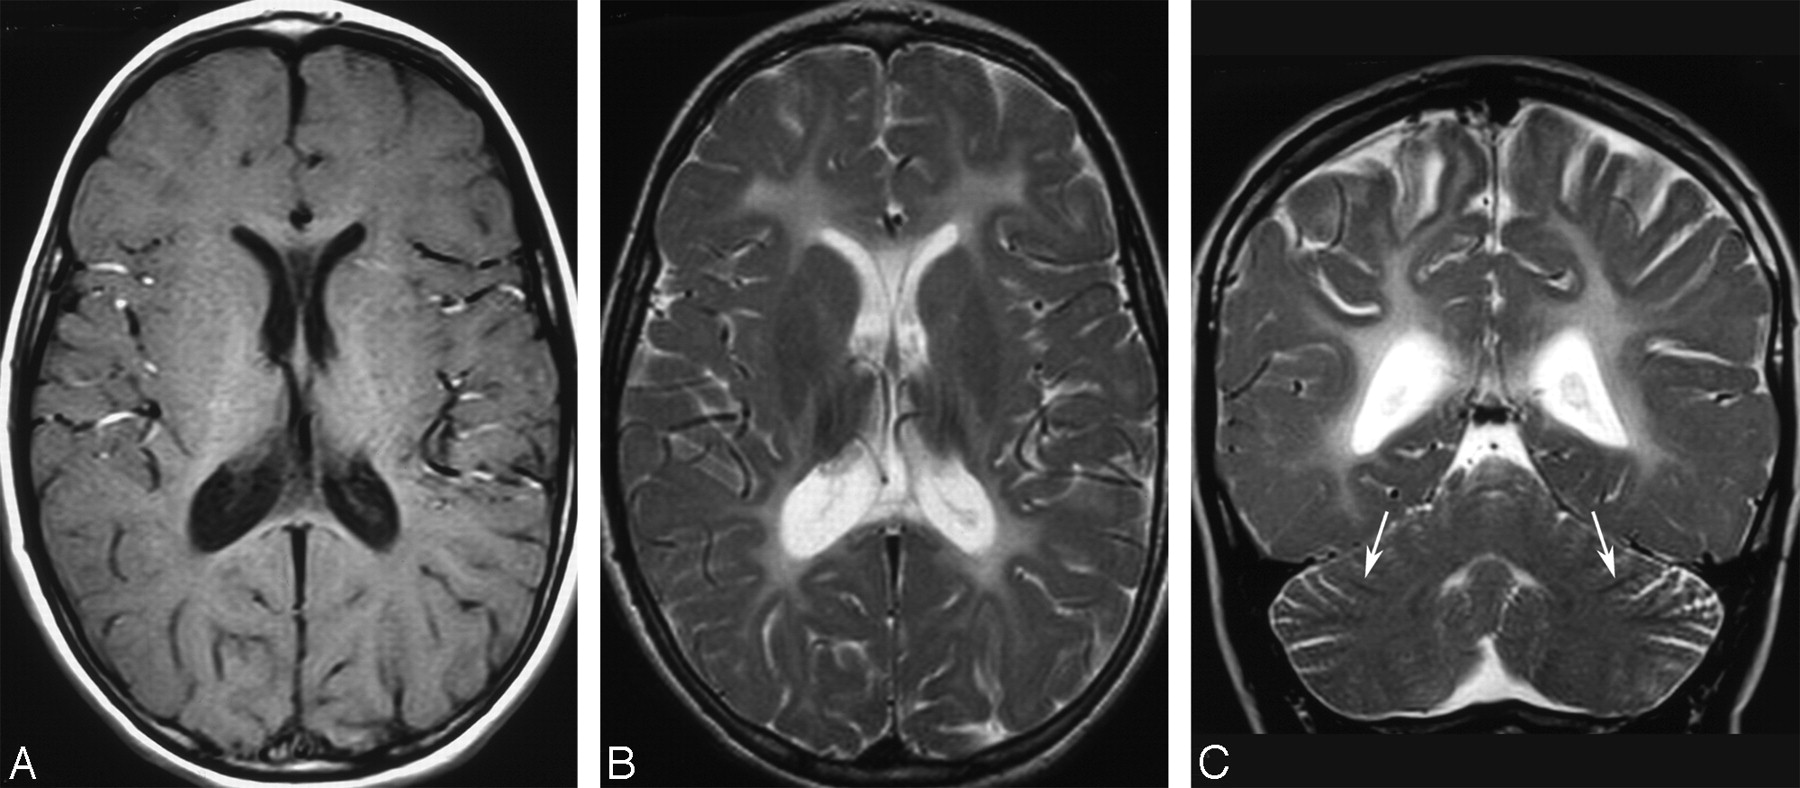

HCC: intermediate stage (patient 6, 8 years of age). A, Axial T1-weighted image (513/12/2, TR/TE/NEX) shows diffuse mild hypointensity of the supratentorial white matter, resulting in blurred gray-white matter interface, consistent with hypomyelination. B, Axial T2-weighted image (4500/108/4, TR/TE/NEX) shows moderate diffuse white matter hyperintensity, also consistent with hypomyelination. Note that the signal intensity is significantly lower than that of CSF. C, Coronal T2-weighted image (4531/112/4, TR/TE/NEX) shows mild hyperintensity of the white cores of the cerebellar hemispheres as well as residual myelination of the medullary laminae (arrows).

The corpus callosum was normal in 2 patients (patients 8 and 9, the youngest in this series) and thinned in the remainder. The cerebellum was normal in size in all patients, and myelination of the medullary laminae was consistently normal. Conversely, in 6 patients, the medullary centers of the cerebellar hemispheres showed mildly increased T2 signal intensity, paralleling that of the adjacent cortical gray matter and resulting in a “blurred” gray-white matter interface (Fig 1). The brain stem was normal in 2 patients (patients 1 and 9); in another 2 patients, the brain stem was normal in size but contained signal-intensity abnormalities, involving the corticospinal tracts (patient 2) and the substantia nigra (patient 8). All the other patients had a moderately hypoplastic pons, associated with hyperintense corticospinal tracts in patient 6 and hyperintense transverse pontine fibers in patient 3. Regarding imaging of the orbits, all patients had already undergone surgery at the time of their neuroimaging studies; as a consequence, changes due to the congenital cataracts could not be evaluated.

An important limitation of the present study is that this is a retrospective review of patients studied at different points in time during their disease course. The reported neuroimaging features are, therefore, heterogeneous and include both early and chronic findings. However, available data suggest at least a gross correlation between the natural progression of the disease and the neuroimaging findings. In the early stage (before 2 years of age), abnormal myelination occurs in the capsular, periventricular, and deep white matter with essential sparing of the subcortical regions (Fig 1). This finding, together with MR spectroscopy and neuropathologic data, may support the contention that little myelin is laid down and that most of it will be broken down (ie, a combination of hypomyelination and demyelination is likely to occur early during the course of the disease). In the intermediate stage (approximately 2–10 years), the white matter is diffusely abnormal with a background of diffuse hypomyelination (Fig 2), in most patients associated with periventricular and deep white matter liquefaction, as shown by both conventional MR imaging and DWI findings (Fig 3). In the chronic stage (second to third decades), the disease progresses toward a burnt-out stage with gliosis and white matter bulk loss (Fig 3). Further studies are required to establish whether the disease can be classified into different stages.